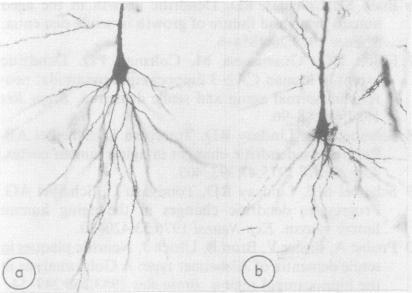

Basal dendrites of hippocampal CA1 pyramidal cells in senile dementia of Alzheimer type (SDAT) were studied quantitatively by the Golgi impregnation method. The present data suggested that basal dendrites of the pyramidal cells were decreased in number in SDAT, and that the dendritic decrease was associated with a decrease in size of their cell bodies.

采用高尔基染色法对阿尔茨海默型老年痴呆(SDAT)患者海马CA1区锥体细胞的基底树突进行了定量研究。目前的数据表明,SDAT患者锥体细胞的基底树突数量减少,且树突减少与其细胞体大小减小有关。